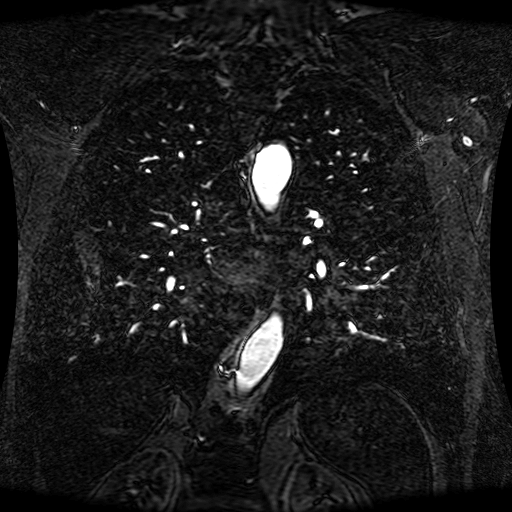

Data Description

These magnetic resonance angiography (MRA) images show coronal slices acquired from consecutive anteroposterior positions within the torso. The study was performed on a 1.5T General Electric (GE) Signa imaging system with gadolinium-contrast-enhancement for visualization of the cardiopulmonary vasculature. The pulse sequence used was a 3D time-of-flight fast spoiled gradient recalled acquisition in steady state (FSPGR, TR=6.3, TE=1.4, NEX=1, FOV = 40cm, slice thickness = 1.2mm).

This sample image contains 76 frames. It is available in DICOM format (E1154S7I.dcm), as an animated GIF (E1154S7I.gif), as .ogg, .mp4, .webm, and .swf animations (one of which is shown above), or as individual PNG-format frames (see below).